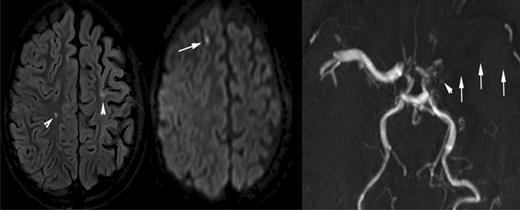

In addition to the varying definitions of SCI, lesion detection is dependent on the magnetic resonance (MR) technique (fluid attenuation inversion recovery [FLAIR] or diffusion-weighted imaging [DWI], see Figure 3, vs traditional T2-weighted images), the slice thickness,11 and the magnetic field strength. As further advances in imaging are made and medical centers transition from 1.5 Tesla to 3.0 Tesla magnets, more individuals with SCA will be detected with SCI, and quantitative techniques are likely to detect subtle abnormality in those without SCI on T2-weighted MRI.12,13 Use of the greater magnet strength will most likely have an impact on measures of incidence and prevalence of SCI, especially in longitudinal studies and CNS-related clinical trials. Thus, investigators must consider the anticipated change in the magnetic strength of the scanner over time when conducting a longitudinal study.

A 10-year-old boy with sickle cell disease and history of acute chest syndrome now presents with pain crisis. MRI of the brain was requested for episodic slurred speech. Axial FLAIR MR image (left) and DWI (middle) illustrate many of the manifestations of SCD in the brain. The arrowheads on the FLAIR image point out areas of old (silent) infarctions in the white matter of the centrum semiovale on the right and at the posterior aspect of the left superior frontal gyrus. The DWI shows an additional area of signal abnormality in the anterior aspect of the right superior frontal gyrus, representing a recent infarction. In addition, there is atrophy of the left cerebral hemisphere, which is seen in the setting of sickle cell–associated vasculopathy manifest by nonvisualization of the left middle cerebral artery by MRA (arrows on the right image). The MRA also shows subtle collaterals (moyamoya vessels) in the lenticulostriate distribution on the left (arrowhead).

As is required by this definition, children with SCI do not have any obvious evidence of symptoms, other than perhaps academic or behavioral difficulties. Quite often, the presence of SCI is detected when the child presents with subtle neurologic findings prompting a brain MRI. The neuroradiologist may identify additional previous infarcts and distinguish an acute cerebral infarct from a previously unknown SCI (Figure 3A). A focal DWI hyperintensity indicates an ischemic injury within the last 8 to 10 days14 (Figure 3B), while the presence of brain atrophy suggests a chronic process.